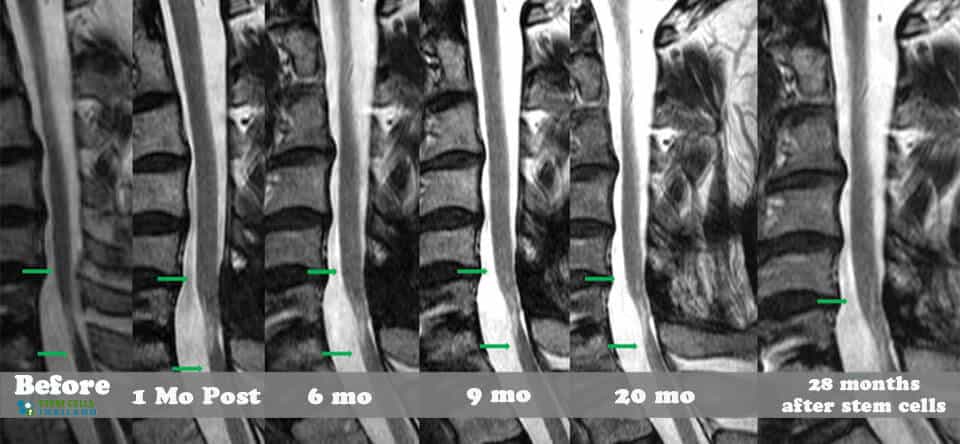

脊髓損傷的細(xì)胞療法側(cè)重于大腦和身體之間軸突的再生,這些軸突在事故發(fā)生后受到嚴(yán)重限制或不存在。我們針對脊髓損傷的干細(xì)胞移植可以幫助患者消除疼痛,恢復(fù)膀胱和腸道功能,恢復(fù)失去的感覺,并再生內(nèi)臟運(yùn)動神經(jīng)元,同時最大限度地減少其他問題,例如損傷引起的痙攣或抑郁。傳統(tǒng)治療不解決再生問題,而是側(cè)重于疼痛管理、康復(fù)和減少繼發(fā)性損傷。

基于細(xì)胞的治療采取更積極主動的方法,通過刺激/增強(qiáng)受損細(xì)胞和組織的修復(fù)來促進(jìn)人類的自然修復(fù)周期。修復(fù)受傷的脊髓和竹脊柱需要超越任何傳統(tǒng)技術(shù)來幫助您恢復(fù)部分/全部失去的功能。臨床試驗(yàn)表明,細(xì)胞更新和死亡是非常正常的,當(dāng)身體細(xì)胞受傷或老化時,細(xì)胞會自然發(fā)生。這些死亡細(xì)胞通常被健康和受損的細(xì)胞包圍。我們針對坐骨神經(jīng)痛和椎管狹窄的治療方案通過利用神經(jīng)生長因子和旁分泌信號傳導(dǎo)的靶向細(xì)胞因子療法,有助于促進(jìn)這些死亡或受傷細(xì)胞的愈合欺騙身體重新開始愈合過程。

我們脊柱損傷治療中心的目標(biāo)是幫助以自然和安全的方式修復(fù)損傷。我們的治療是在細(xì)胞水平上進(jìn)行的,僅影響靠近影響點(diǎn)的區(qū)域。如果受傷時間不到兩年,積極的結(jié)果可能會非常顯著。對于那些患有老年損傷、創(chuàng)傷性腦損傷、嚴(yán)重椎間盤退變、股骨頭壞死、周圍神經(jīng)病變或脊髓性肌肉萎縮的人來說,隨著時間的推移,完全康復(fù)的機(jī)會變得更加困難。

組織、軟骨或韌帶的新?lián)p傷對干細(xì)胞治療的反應(yīng)要好得多。治療后的康復(fù)需要大量的奉獻(xiàn)和康復(fù)訓(xùn)練。初次治療后約2-3個月,身體改善明顯,且效果是永久性的。[2]